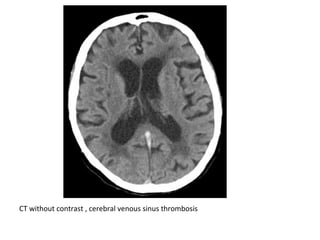

CT without contrast , cerebral venous thrombosis

CT without contrast , cerebral venous sinus thrombosis